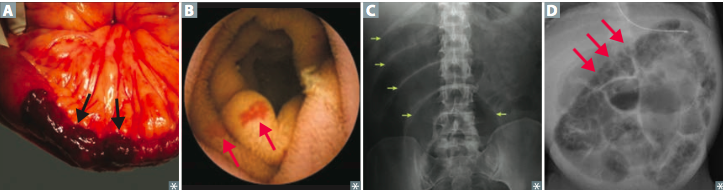

demonstrates the gross findings with Crohn’s disease. T

the small intestine–and the terminal ileum in particular–is most likely to be involved.

The middle portion of bowel seen here has a thickened wall and the mucosa has lost the regular folds. The serosal surface demonstrates reddish indurated adipose tissue that creeps over the surface.

Serosal inflammation leads to adhesions. The areas of inflammation tend to be discontinuous throughout the bowel

A

B

C

D

Small bowl necrosis seen in

Acute mesenteric ischemia

hematochezia

pneumatosis intestinalis

Chrohn: String sign on barrium swollow

creeping fat, bowel wall thickening (“string sign” on barium swallow x-ray A ), linear ulcers, fissures.

Chrons–> Crohn’s disease of the colon showing thickening of the wall, with stenosis, linear serpiginous ulcers and cobblestoning of the mucosa.